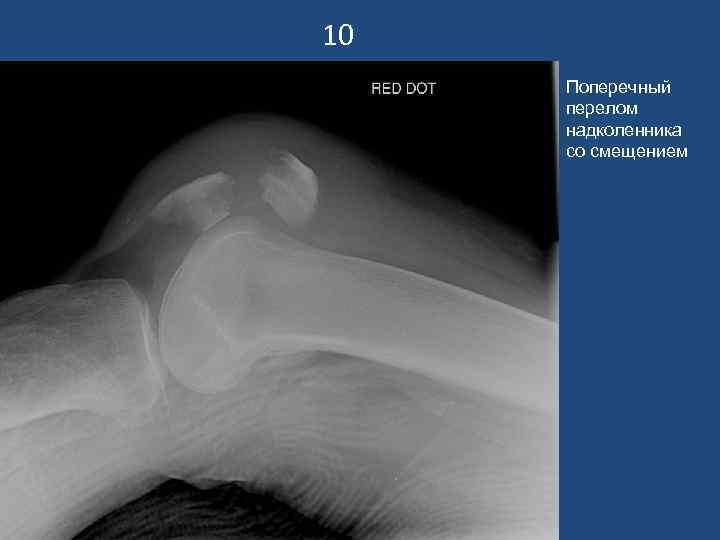

10 Поперечный перелом надколенника со смещением